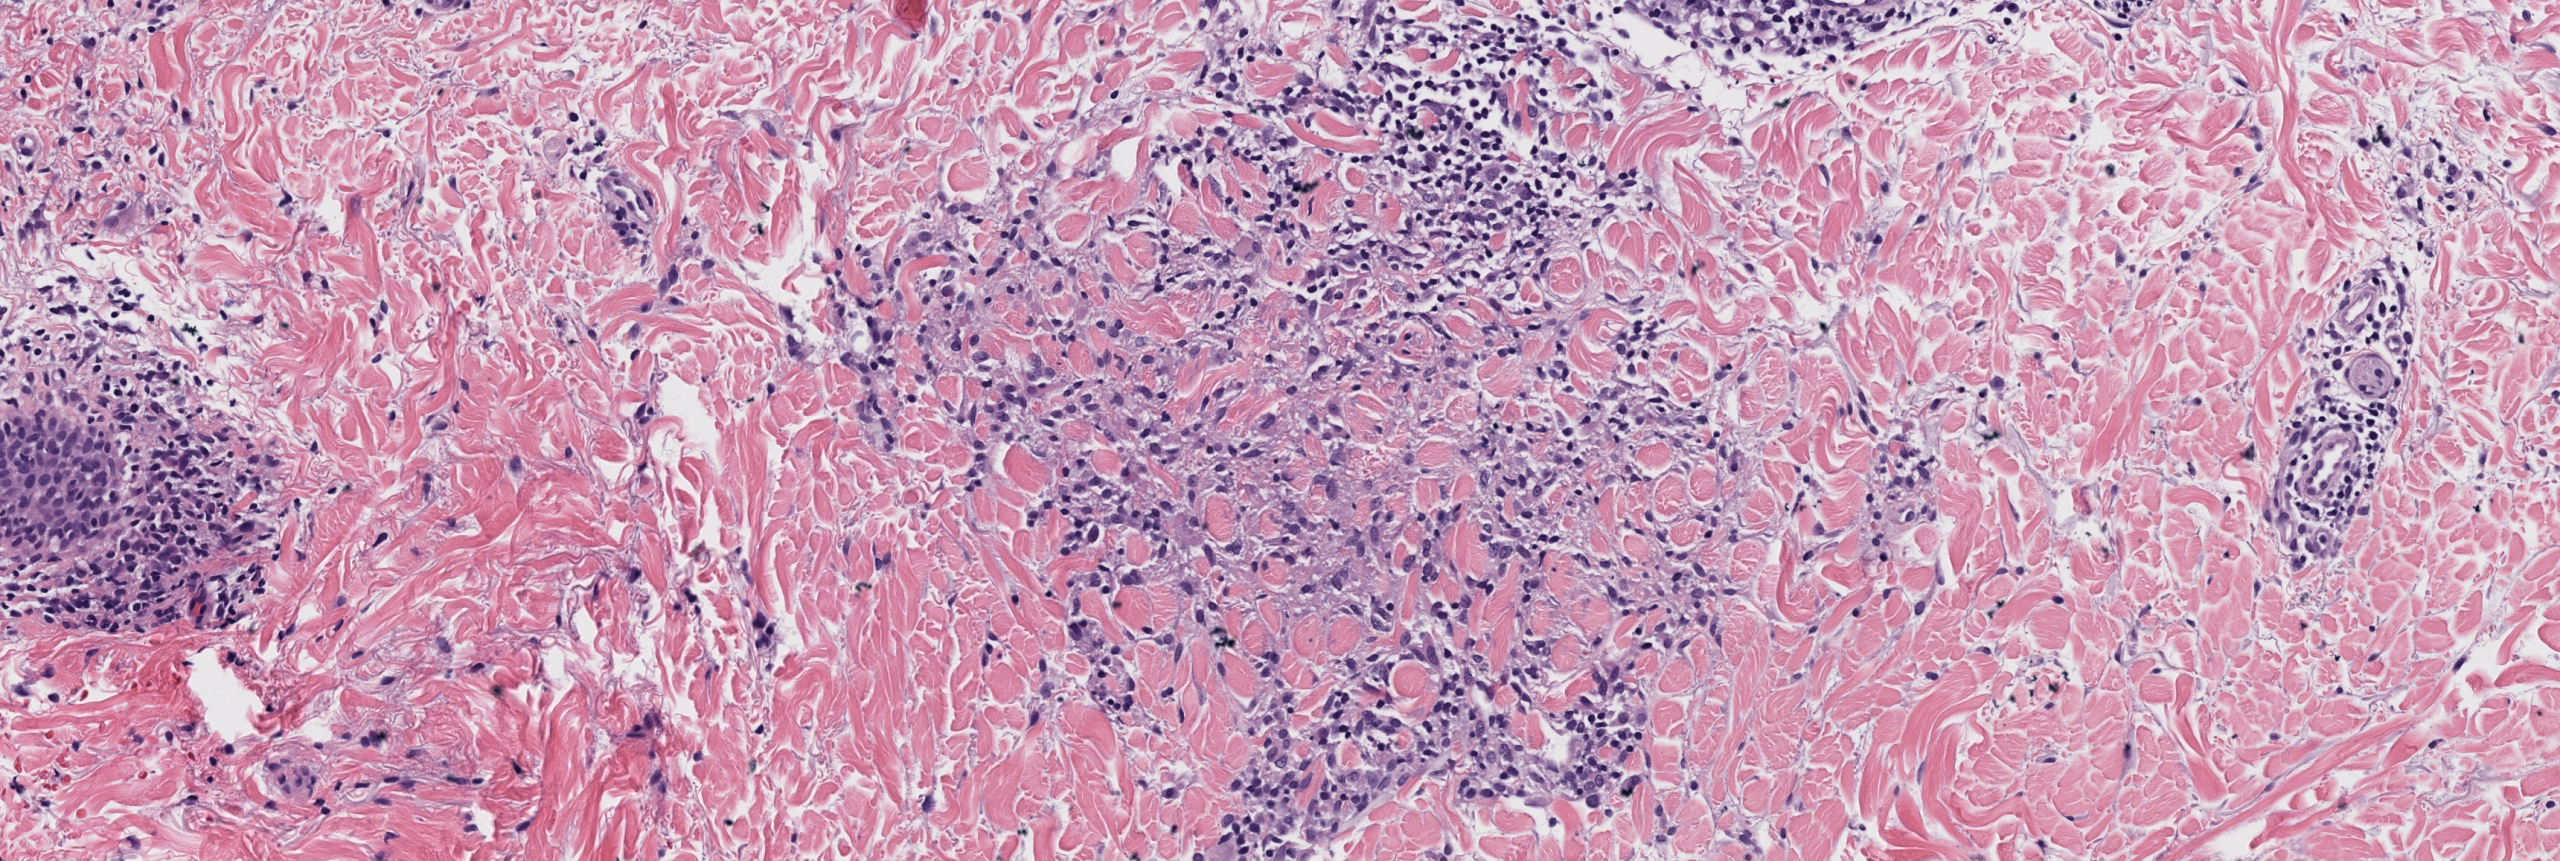

[Image 2: Medium power showing interstitial lymphohistiocytic infiltrate]

This is patch-type granuloma annulare, an uncommon but increasingly recognized variant of classic GA. The diagnosis is confirmed by the interstitial pattern of bland mononuclear histiocytes dissecting between preserved collagen bundles with increased dermal mucin and absence of epidermal changes or palisaded granulomas.